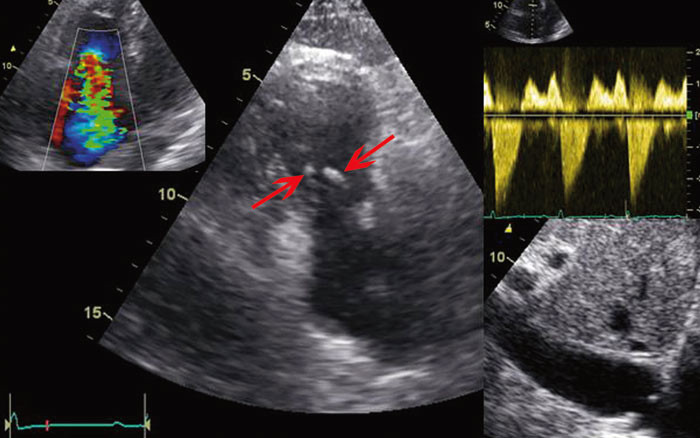

Siden hypoksemien kunne være utrykk for at blodet ble shuntet fra venøst til systemisk kretsløp, ble det injisert agitert saltvannsoppløsning (luftmikrobobler) i perifer vene. Umiddelbar påvisning av «kontrast» i venstre atrium antydet at det var en stor kontrastpassasje på forkammernivå (fig 1). En slik shunting av venøst blod til venstre hjertekammer kunne forklare pasientens hypoksemi og tungpust. For å kartlegge årsaksforholdene nærmere ble det utført transøsofageal ekkokardiografi da denne metoden gir høyere bildeoppløsning. Undersøkelsen avdekket et åpent (patent) foramen ovale (fig 2).

Hyppigheten av åpent foramen ovale i normalbefolkningen er 25 – 30 % (2, 3). Ved normale trykkforhold i hjertet vil åpent foramen ovale ikke medføre betydelig grad av shunting av venøst blod (4). Vår pasient hadde flere ekkokardiografiske tegn på trykk-volum-belastning av høyre hjertehalvdel: venestuving, dilatert v. cava, V-bølge, bukende atrieseptum og høye antegrade hastigheter over trikuspidalostiet. Derfor ønsket man bedre visualisering av trikuspidalklaffen.